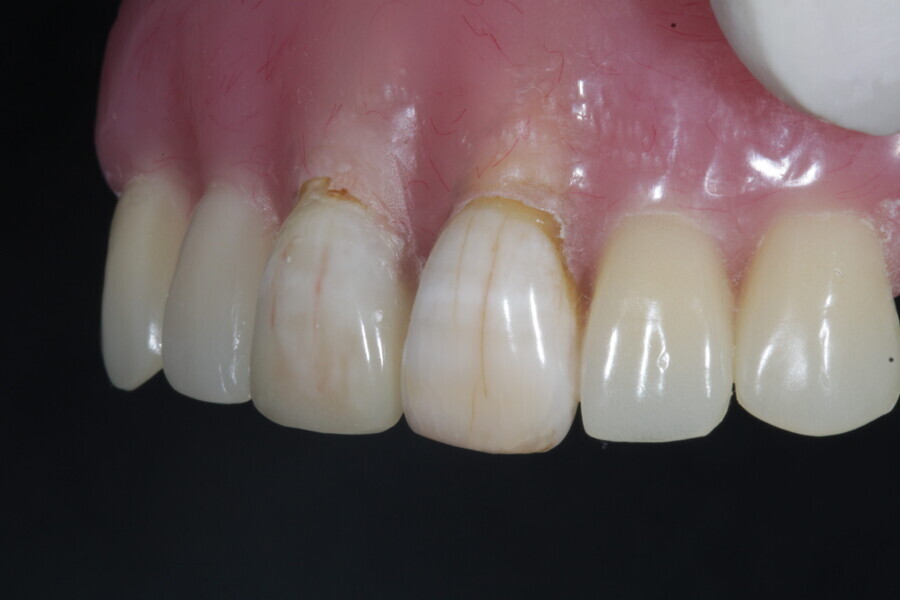

1. functional and aesthetic reconstruction of a maxillary anterior tooth using fibre-reinforced flexible micro-posts after endodontic treatment (Figs. 3–20);

Example 1—showing functional and aesthetic reconstruction of a maxillary anterior tooth using fibre-reinforced flexible micro-posts after endodontic treatment.